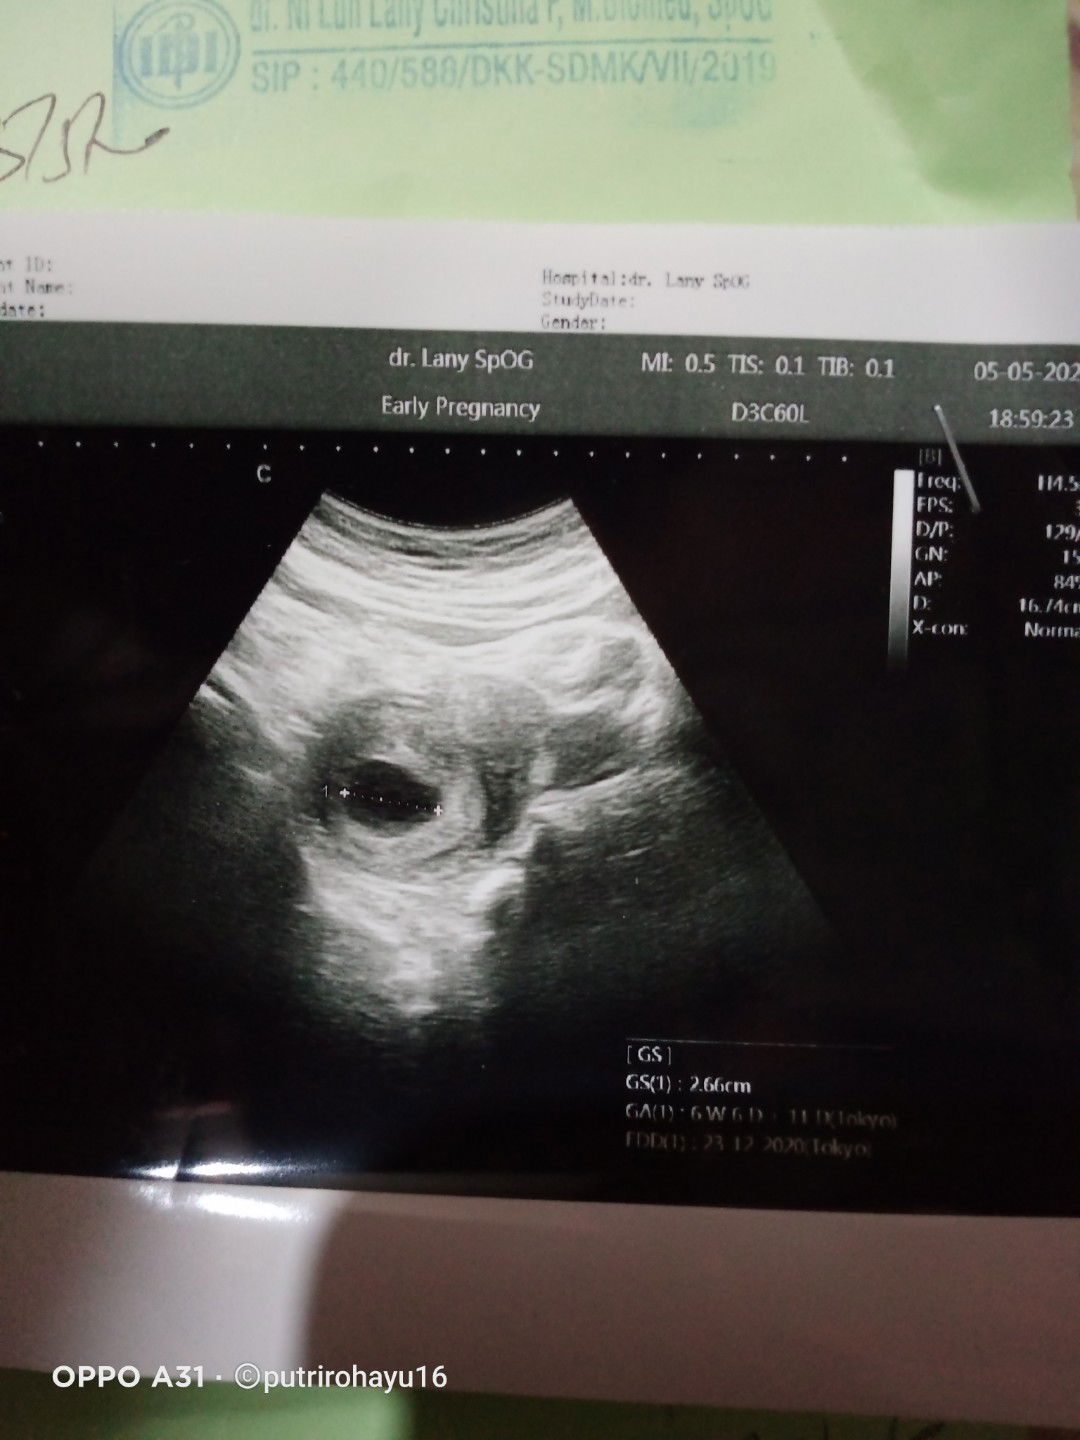

Udh 2 minggu tp blm kelihtn jenis klaminya

2 mggu blm jadi apa apaa.mba